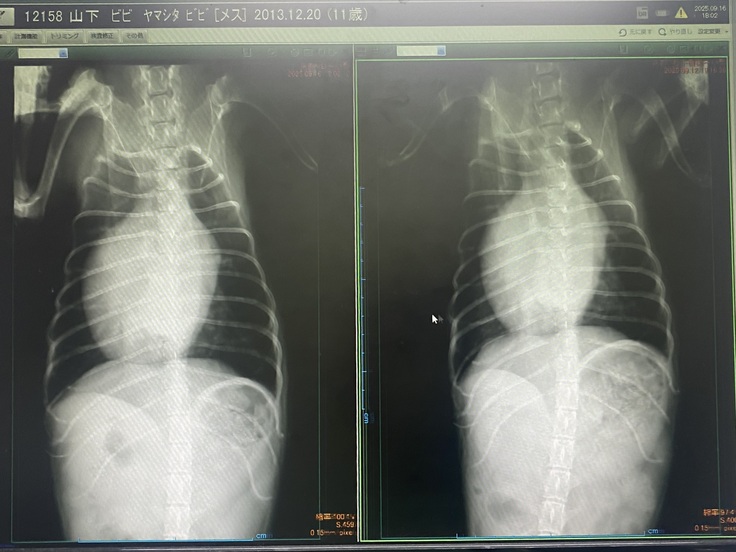

その時に撮ったレントゲンです。

ビビとの日々が終わってしまう現実を突きつけられました。

ビビは、ステージCとステージDのギリギリのラインで、手術するなら

急がないと危険だというお話でした。